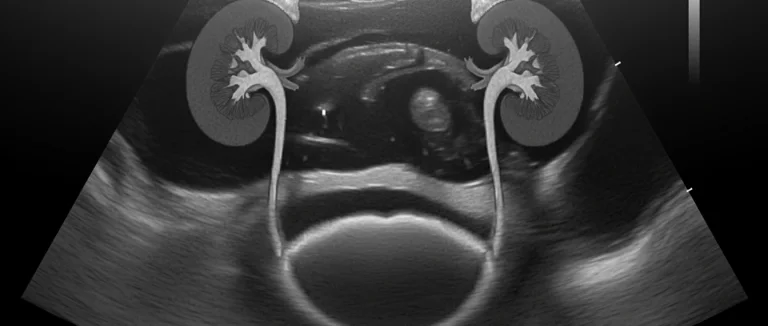

- УЗИ почек и мочевого пузыря – быстрый и безболезненный способ оценить структуру органов.

- КТ или МРТ брюшной полости – используется при подозрении на опухоли или аномалии развития.